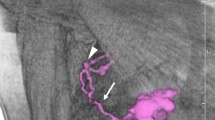

Patients (228) with newly diagnosed rectal cancer, confirmed by biopsy, underwent enhanced computed tomography (CT). Patients were assigned to the benign node or malignant node group according to histopathological analysis of node samples. All CT-detected lymph nodes were segmented using the edge detection method, and seven quantitative parameters of each node were measured. To increase the prediction accuracy, a hierarchical model combining the merits of the support and relevance vector machines was proposed to achieve higher performance.

Quantitative measurements of lymph nodes

To achieve comprehensive characterization of a lymph node, 19 parameters were computed automatically based on segmented image. Among which seven were chosen to consist of a compact but highly representative subset. The detailed definitions of the parameters are listed below:

-

Area: the area of the node;

-

Major axis length & minor axis length: the major & minor axis of the ellipse that covers the node with same normalized second central moments;

-

Solidity: the ratio of the area of the node and its convex area;

-

Density: the ratio between the summation of grey value within the node and its area;

-

Heterogeneity: Fraction of pixels that deviate more than a certain range (10% default) from the average intensity.

-

Fractal dimension: Minkowski dimension of the boundary of the node, computed by box-counting method.

-

Minkowski dimension: a way of determining the fractal dimension of set S in a Euclidean space Rn. It is estimated by limit of \( {\lim_{{\tau \to 0}}}\frac{{{N_{\tau }}}}{{1/\varepsilon }} \), where N(ε) is the number of boxes of side length ε required to cover the set S.